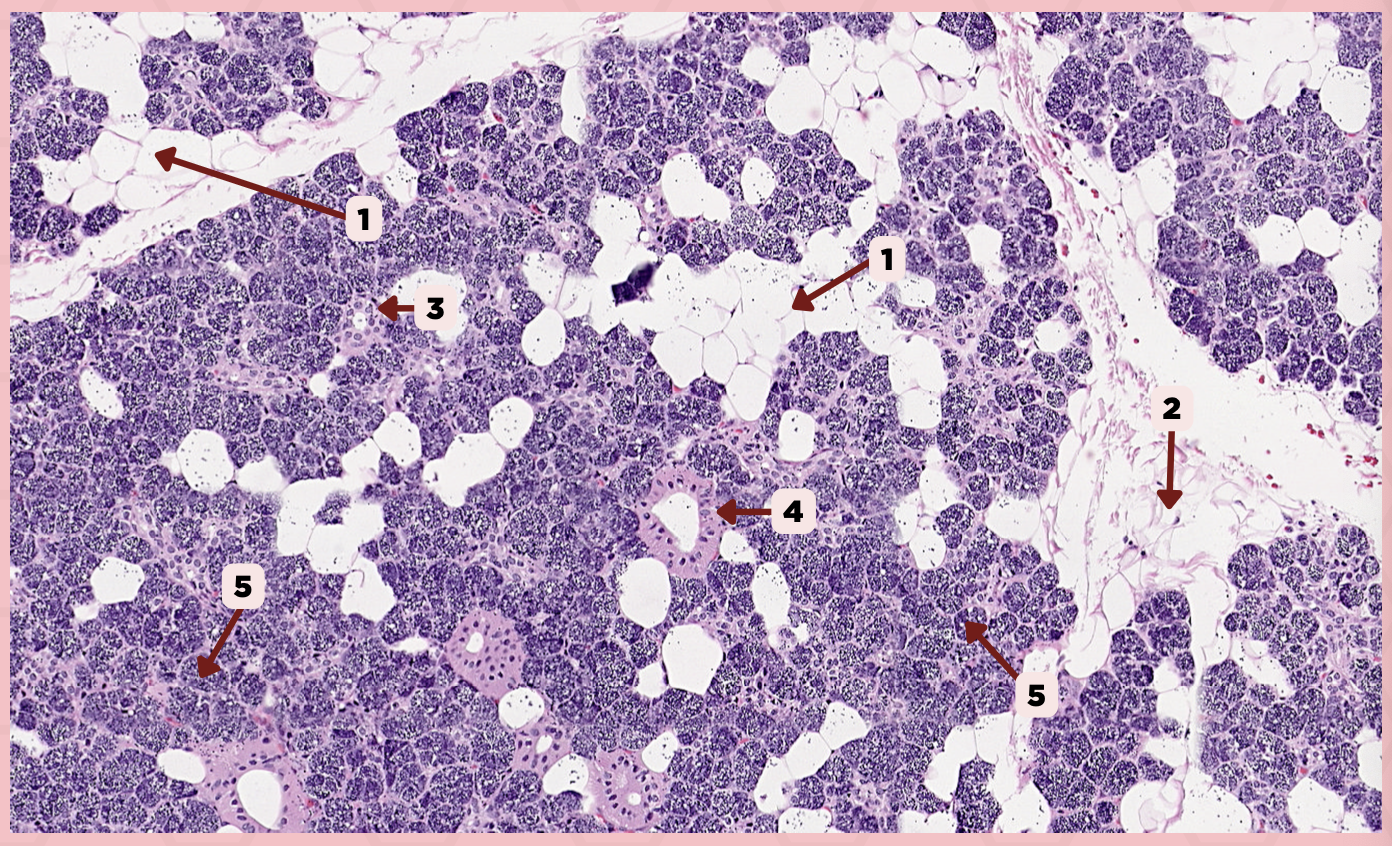

Parotid

Identify the specimen.

Vein

Identify the structure labeled as 1.

Artery

Identify the structure labeled as 2.

Nerve

Identify the structure labeled as 3.

Interlobular Septa

Identify the structure labeled as 4.

Interlobular Duct

Identify the structure labeled as 5.